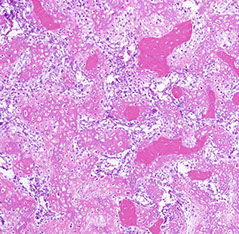

Aneurysmal bone cyst (ABC)

- usually an impressive, "benign" expansile lesion that destroys bone; etiology unknown, prolly a rxn to interosseous hemorrhage

- seen in pts <20 yo, presenting c pain, swelling, MC in metaphysis

Imaging: MC in metaphysis of long bones or posterior aspect of vertebra, "soap bubble" characteristic

- CT shows thin rim of sclerosis at margins, and can have fluid-fluid levels (double meniscus 2/2 old blood c lighter overlying watery fluid, or can have soap-bublle appearance

Micro: if intact, see cavernous blood-filled spaces lined by fibrous septae

- septae made of loose / edematous tissue c spindle cells, giant cells, capillaries and thin strands of osteoid or bone + mixed inflam

- can have lots o mits, but not that much atypia

Genes: 70% of primary (but not secondary) lesions have USP6 gene chromosome on 17p13.2 (meaning they may actually be unusual lesions (nodular fasciitis has same MYH9-USP6 17;22)

Tx: Exision vs curettage

Px: Rare recurrences